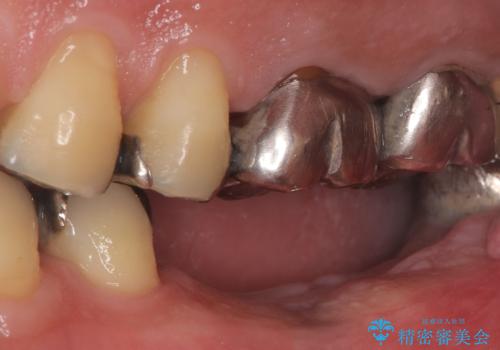

- 治療計画

今回の治療では、まず左下6番と7番の欠損部に、骨の状態を考慮しながら慎重に2本のインプラントを埋入しました。インプラント体と骨がしっかりと結合するのを待った後、最短の期間で最終的な被せ物を装着するための精密な型取りを実施。最終的に、周囲の歯と調和した審美性の高いセラミック製の歯を装着しました。